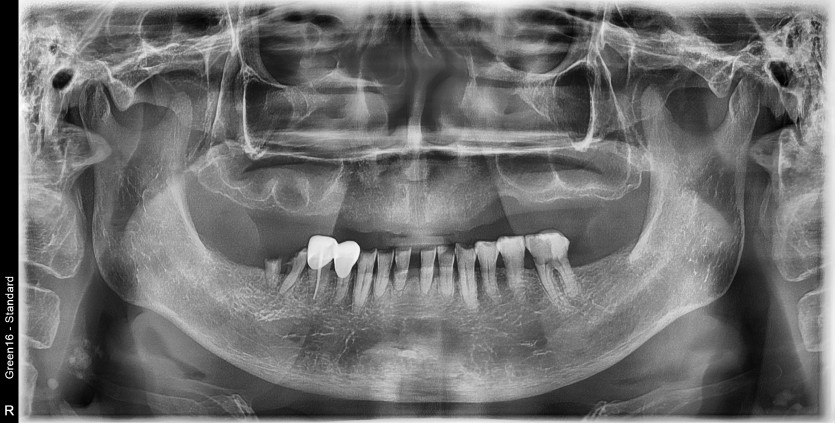

상악 풀아치 증례입니다.

8개의 임플란트로 완성하였습니다.